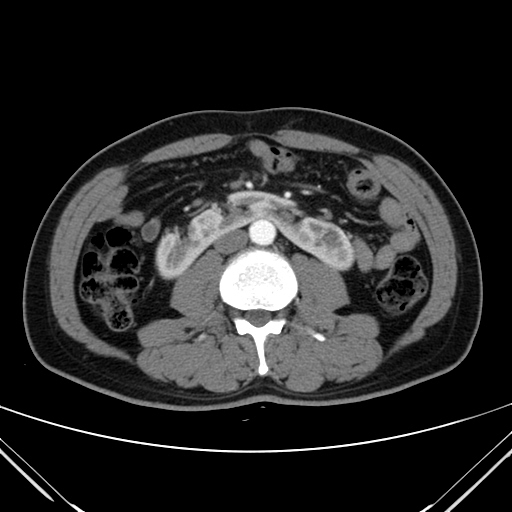

»çÁøCT/MRI

Æó¾Ï